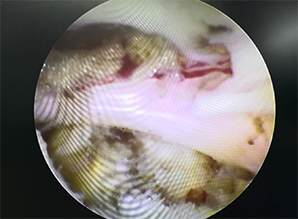

為迅速緩解患者癥狀,根據患者病情并結合影像學診斷,習超杰院長、非手術治療毛珺珺主任為患者制定了目前醫院最新微創手術方案UBE技術下經皮穿刺頸腰椎間盤切除術”。并為林先生家屬說明手術情況后,92620:00習超杰院長、非手術治療毛珺珺主任團隊的共同努力下,在透視下將UBE內鏡放入到腰椎間盤脫出部位,使用UBE專用器械靶精確定位,將神經根和硬膜囊牽向內側并保護起來后,精確摘除突出椎間盤,術中出血少約100ml,沒有出現其他異樣,23:30林先生手術非常成功,術后僅留下21厘米小切口,麻醉過后也并無異常。

UBE是脊柱微創技術,適用于頸椎、胸椎、腰椎的退行性病變。與椎間孔鏡的單通道不同,該技術通常建立兩個通道,一個為觀察通道,一個器械操作通道。觀察通道一般會用到0°或30°UBE內鏡,操作通道可以應用常規的脊柱外科及運動醫學的器械如刮匙、磨鉆、UBE刨刀、UBE射頻消融電極、椎板咬骨鉗、髓核鉗、神經拉鉤等。當然有專門的器械包,甚至可以通過UBE技術完成鏡下融合手術。

4、水介質中操作,視野更加清晰,特殊器械可保持順暢出水;